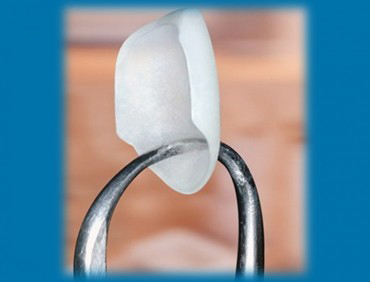

ونیر چیست؟

ونیر لمینیت دندان پوسته باریکی است که ظاهری طبیعی به دندان میدهد و خاصیت ترمیم پذیری و استحکامی مشابه مینای طبیعی دندان را ایجاد میکند. ونیر دقیقاً متناسب با شکل طبیعی دندان تهیه و روی مینای اصلی دندان چسبانده میشود.